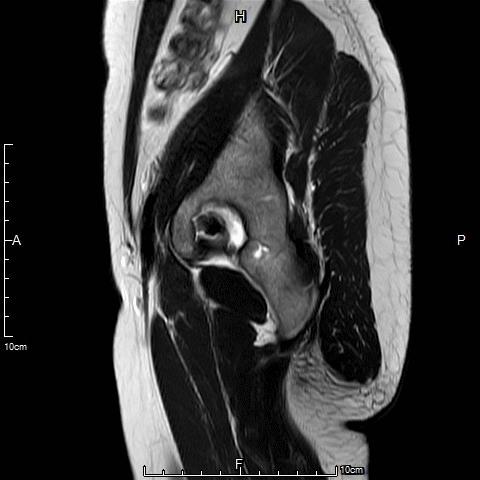

例2

中年女性,痛经10余年,近3个月明显加重。痛经达重度疼痛,严重影响生活质量。磁共振检查显示子宫前壁囊性病灶。临床诊断为囊性子宫腺肌症。